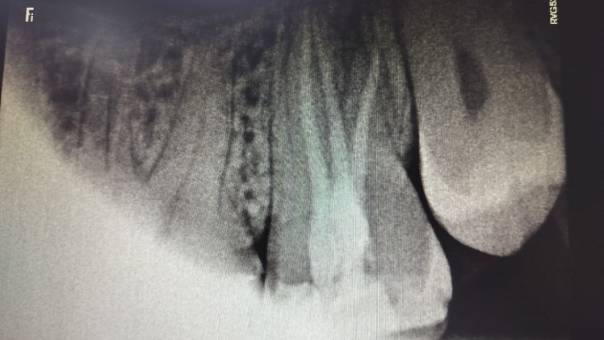

Unfilled distal canal pre-operation

Our Treatment Approach:

After discussing the findings with the patient, we

recommended a Re-RCT, focusing on the missed distal

canal. This would allow us to eliminate the

infection and restore the tooth’s health.